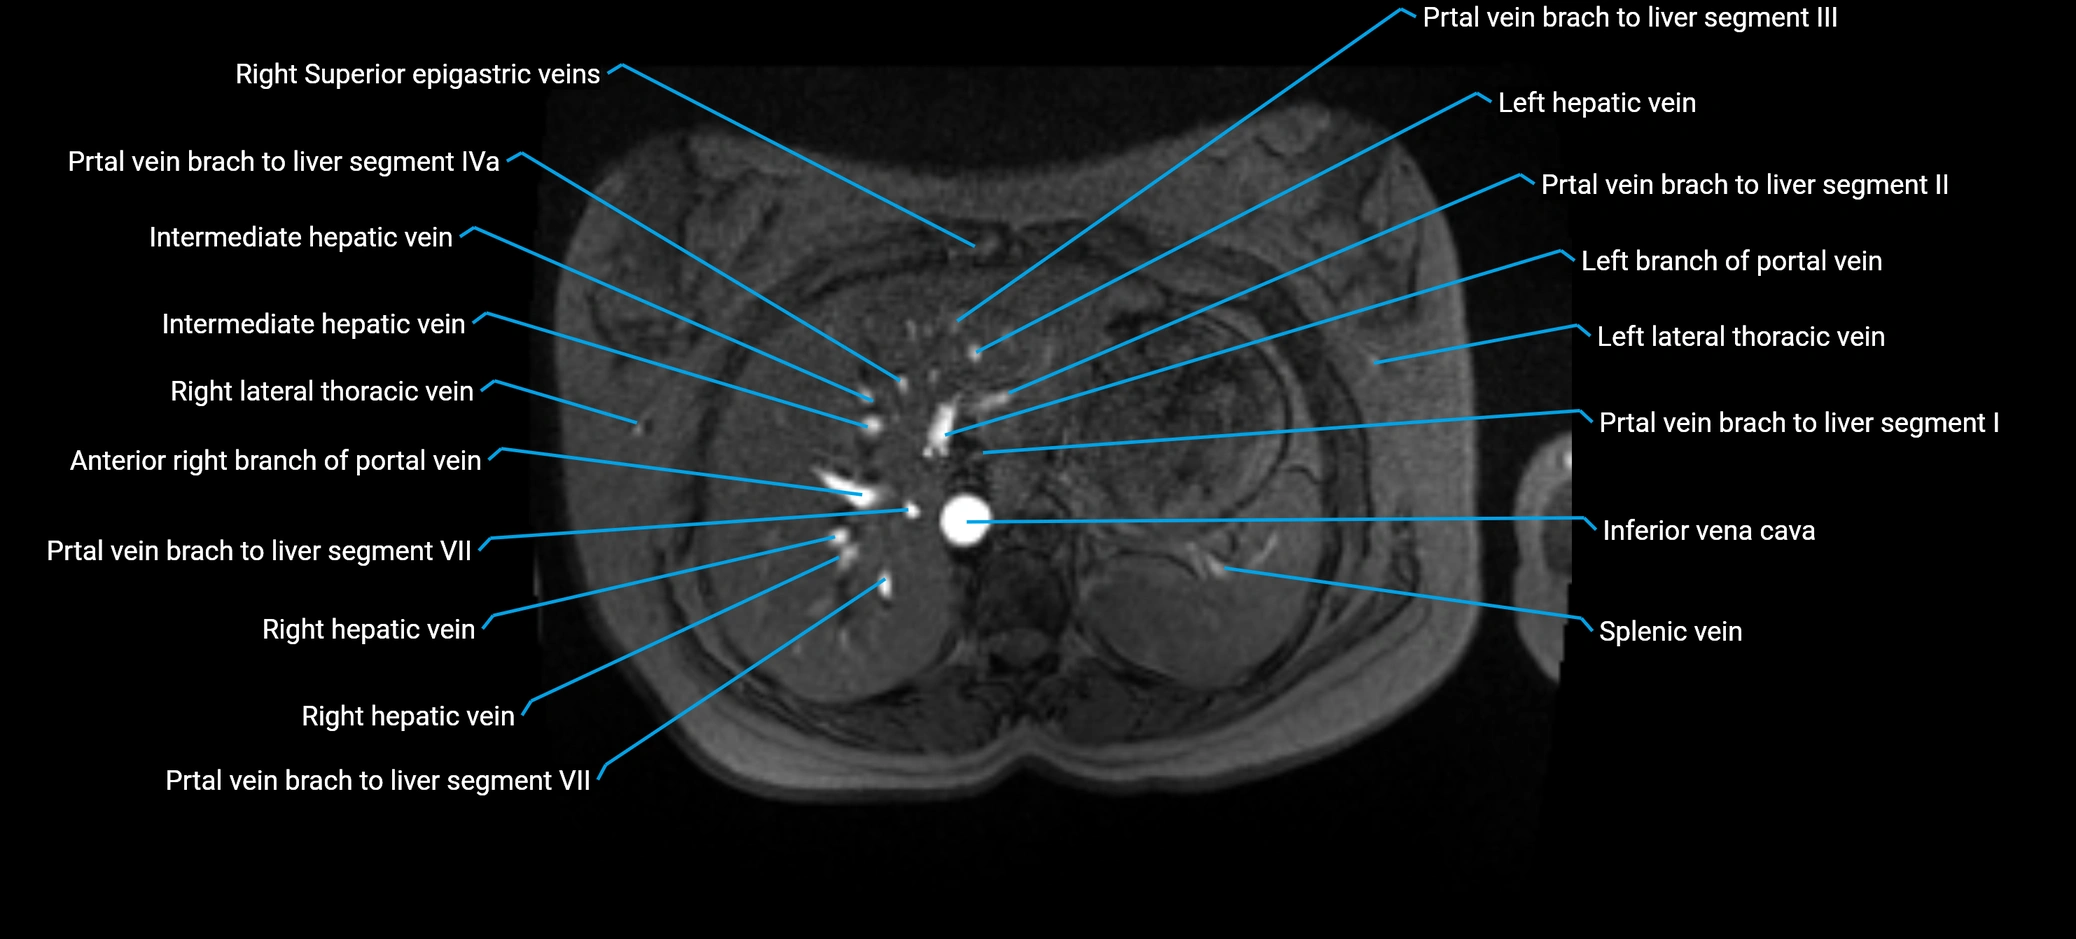

MRI image

image